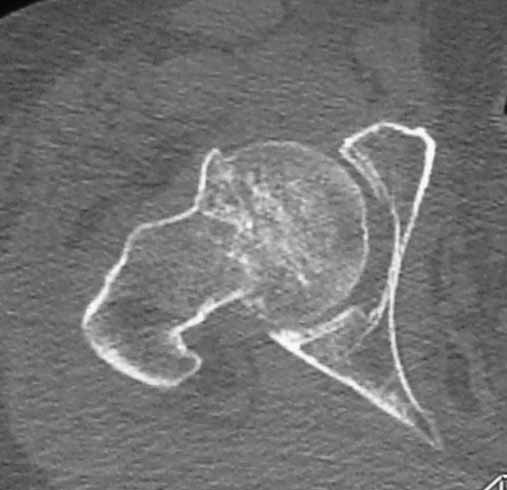

Пациентка 53 лет. ДТП 09.01.12: сочетанная травма: перелом 2-5 ребер справа, ушиб легких;

перелом обеих лонных костей без смещения; закрытый перелом проксимального конца правой

бедренной кости; открытый оскольчатый внутрисуставной перелом проксимальных концов

костей правой голени.

Бедро одномоментно делать не стал, не было уверенности в наличии перелома на уровне шейки. Во время операции смотрел тазобедренный сустав под ЭОПом,

головка неподвижна. После операции повторили КТ, стало очевидно, что имеется субкапитальный перелом. Что делать, остесинтез или протезирование? Если остеосинтез, то чем? Заранее благодарен за советы.